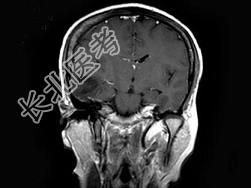

- 单项选择题女,25岁, 头痛3个月,头颅MRI平扫及增强扫描如图, 最可能的诊断是 ( )